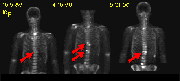

The above scans are from a patient with treated osteosarcoma. The X Ray reveals a sclerotic lesion in the left iliac wing (yellow arrow). The 18F- shows intense uptake in the left calvarium and iliac wing (red arrow), and right inferior sacral joint, suggesting stimulated osteoblastic activity. However, no corresponding focal increases in FDG metabolism are seen (red boxes). These findings are consistent with treated disease. Note that the asymmetry of FDG uptake in the muscles of the lower extremities (green arrows) is due to the patient's ambulation with a prosthetic limb device. The intense metabolic activity of ambulated skeletal muscle stresses the importance of the patient remaining inactive during the uptake period after FDG injection.